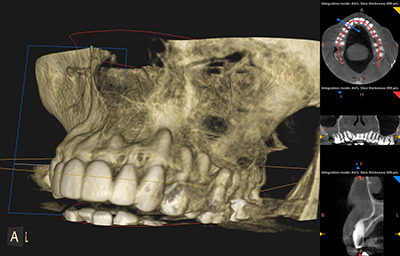

1Smile Dental uses 3D CBCT imaging to evaluate wisdom teeth with precision. This allows us to:

This advanced imaging is especially important for complex or deeply impacted wisdom teeth.